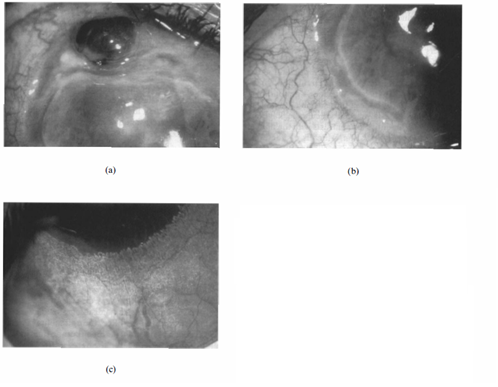

Mooren’s ulcer is characterized by painful peripheral corneal ulceration of unknown etiology. The disease generally begins with intense limbal inflammation and swelling in the episclera and conjunctiva [1]. Corneal changes begin within 2-3 mm from the limbus, first appearing as grey swellings that rapidly furrow, affecting the superficial one-third of the cornea and then proceeding circumferentially and centrally over 4-12 months. [1][2] The bed of the furrow becomes vascularized, with vessels advancing into the base of the undermined edges of the ulcers [1] (figure 1). These ulcers are often described as crescent-shaped and can leave behind an opaque and edematous central cornea. Alternatively, they can completely consume the corneal stroma, replacing it with a thin fibrovascular membrane. [3] Inflammation is not seen in the sclera adjacent to the peripheral ulcers, nor does it affect the underlying Descemet’s membrane. [4] Destruction of the cornea generally affects stromal tissue only, leaving behind an intact endothelium and epithelium. [5] The central edges of the ulcer can develop an overhanging edge with or without opacification, and neovascularization of the cornea can occur, extending from the limbus into the ulcer bed. [3] Neovascularization can occur up to the advancing edge of the ulcer but not beyond it. [5]

The diagnosis of Mooren's ulcer requires the absence of any ocular infection or systemic rheumatological diseases known to cause peripheral corneal ulceration [3]. Srinivasan and colleagues described three patterns of ulceration: partial peripheral, complete peripheral, and total corneal ulceration (Figure 3). In complete peripheral ulceration, the disease process has completely encompassed the corneal periphery, leaving behind a “central island of cornea” often opacified (Figure 3b). In total corneal ulceration, the corneal stroma has been completely replaced with a fibrovascular membrane (Figure 3c). Partial peripheral ulceration can be subdivided into nasal, temporal, superior, and inferior ulceration, of which temporal and nasal (the so-called intrapalpebral cornea) involvement is more common [3].